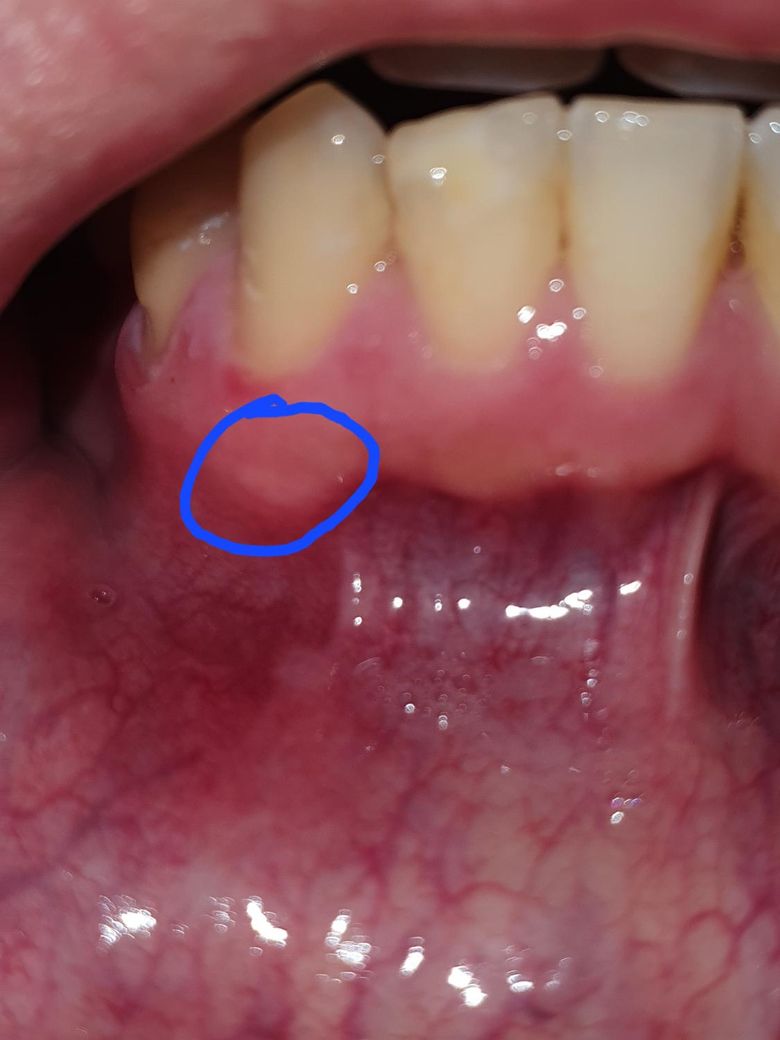

이거 구내염일까요 잇몸 염증일까요?

한 일주일 전부터 생겼다가 슬슬 가라앉는 중에 찍은거긴 한데 혹시 구내염일까요 아니면 잇몸 염증일까요? 혹시 염증이라면 치아 뿌리에서부터 나는걸까요?

잇몸에서 원인된 것은 아니며, 단순표재성 구내염으로 보입니다. 구내염은 시간이 지나면 저절로 없어집니다.

사진상으로 염증은 아니고 자극을 받아서 생긴 구내염같습니다. 자극이 가지 않도록 해주시면 시간이 지나면 괜찮아 지실꺼에요.

사진으로만 봤을 경우에는 크게 문제가 없어 보입니다. 치조골이 바깥으로 자라 나온 경우에는 해당 부위가 밝게 보이는 경우가 있습니다.

치아 뿌리 주변에 뼈가 있어서 해당 부위가 다른부위들보다 좀 더 튀어나와있는데요. 그러다보니 잘 쓸리고 상처가 나서 구내염이 생기기 쉽습니다.

일반 구내염의 양상으로 보시면 될 것 같습니다. 일반적인 구내염은 1~2주 안에 증상 완화됩니다.